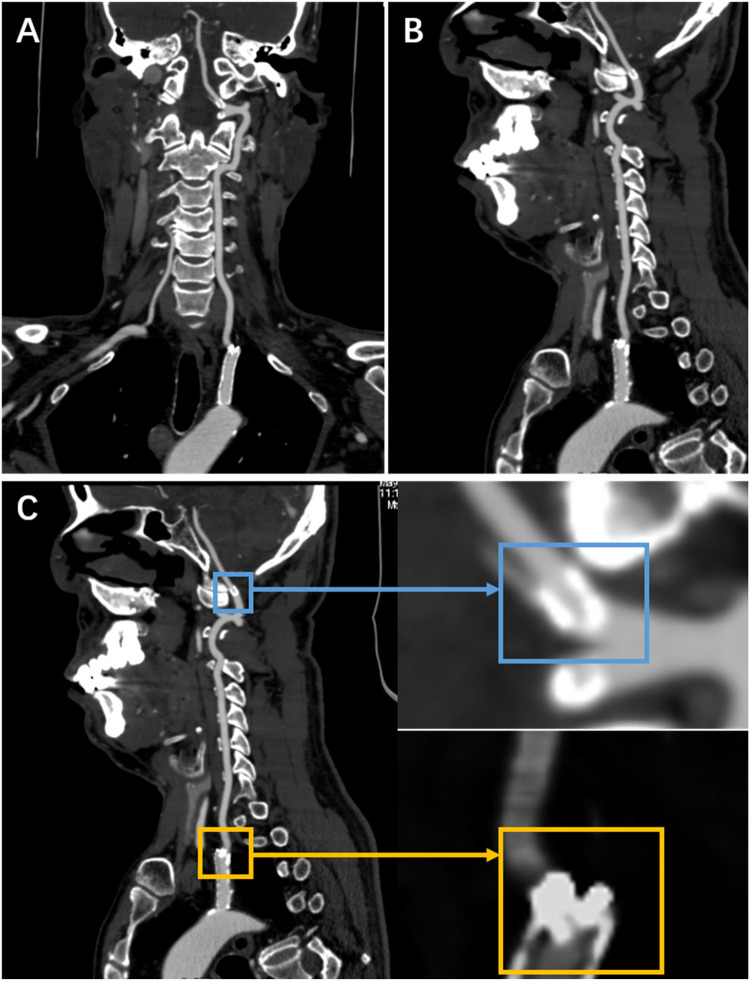

导言:支架骨折是一种公认但罕见的与椎动脉起源支架相关的并发症。方法:我们报告一位因眩晕和复视而被诊断为左椎动脉源性狭窄的男性患者,他使用了雷帕霉素洗脱支架。1年随访的计算机断层血管造影显示支架中部骨折伴远端碎片向V3节段迁移,但患者无症状,并在密切监测下进行医学治疗。结果:本病例说明雷帕霉素洗脱支架是治疗椎动脉起源狭窄的有效方法。讨论:在涉及支架完全骨折和远端碎片迁移的罕见病例中,保守治疗可能是无症状患者的可行选择。

Methods: We present a male who was diagnosed with left vertebral artery origin stenosis due to vertigo and diplopia, and who was deployed with a rapamycin-eluting stent. One-year follow-up computed tomography angiography demonstrated mid-stent fracture with distal fragment migration into the V3 segment, but the patient was asymptomatic and managed medically with close surveillance.